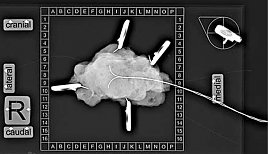

Notwendiges Equipment für die stereotaktische Biopsie mit Biopsieeinheit (Foto: SHK) Notwendiges Equipment für die stereotaktische Biopsie mit Biopsieeinheit (Foto: SHK) Notwendiges Equipment für die stereotaktische Biopsie mit Biopsieeinheit